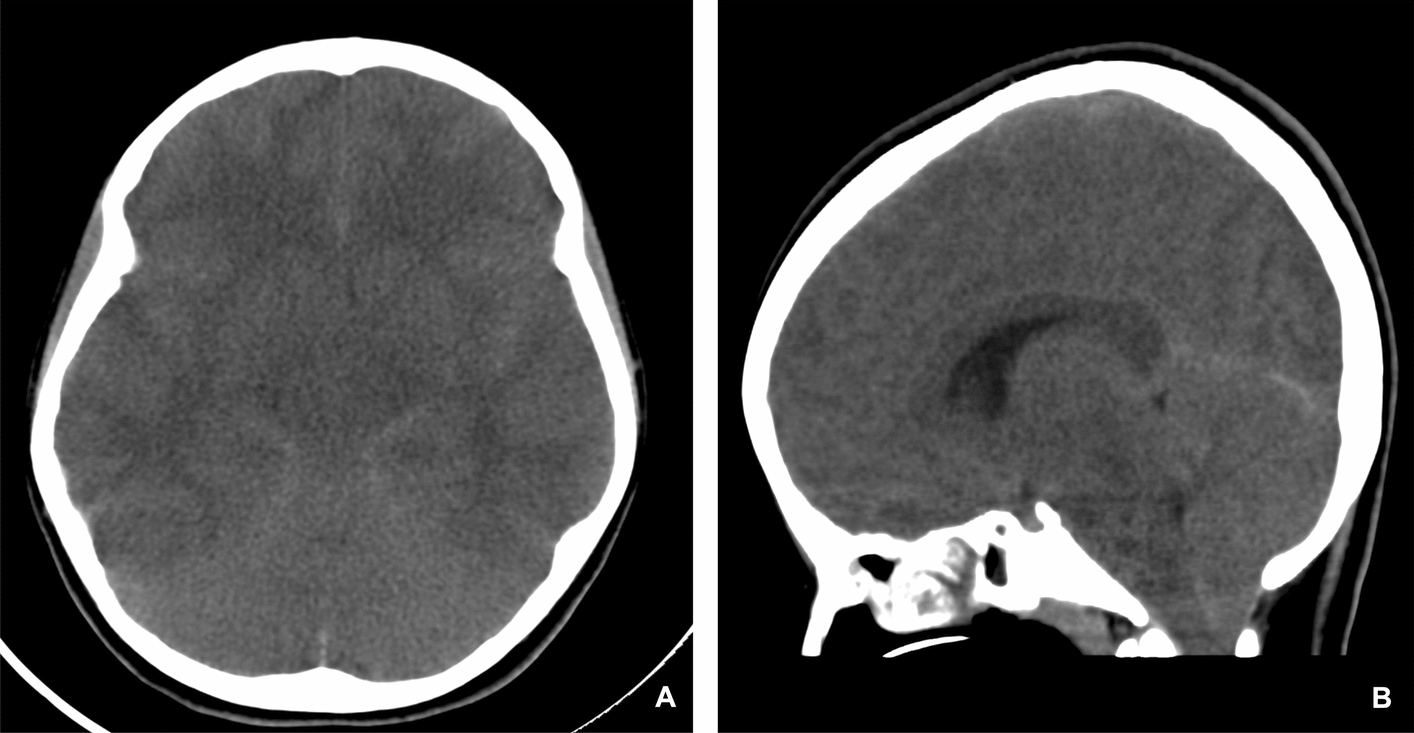

Case presentation: We report the case of a 12-year-old girl of Middle Eastern descent from Saudi Arabia with a history of bronchial asthma and allergic rhinitis who developed cerebral edema and resultant tonsillar herniation following a severe asthma exacerbation. Her presentation was marked by respiratory distress unresponsive to initial therapy. Intensive management in the pediatric intensive care unit including mechanical ventilation and neuroprotective measures resulted in full neurological recovery prior to discharge.